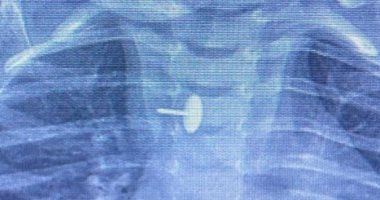

تمكن فريق جراحة الأطفال بمستشفى الأطفال التخصصي ببنها في محافظة القليوبية من إجراء عملية جراحية متقدمة لاستخراج دبوس ضغط من مريء طفلة تبلغ من العمر سنة وسبعة أشهر. كانت الطفلة قد ابتلعت الدبوس منذ ستة أشهر، مما شكل خطرًا على حياتها واستدعى التدخل الطبي الفوري.

أوضحت المستشفى أن الدبوس استقر داخل جدار المريء، مما أدى إلى صعوبة في البلع للطفلة طوال هذه المدة وعرّض حياتها للخطر. وتمت العملية باستخدام أجهزة حديثة مثل منظار الجهاز الهضمي وجهاز الأشعة “سي- آرم” ومنظار القصبة الهوائية، وضم فريق الجراحة الدكتور محمد متولي والدكتور وليد محمد والدكتور عبد الله أحمد والدكتور السيد الوصال.